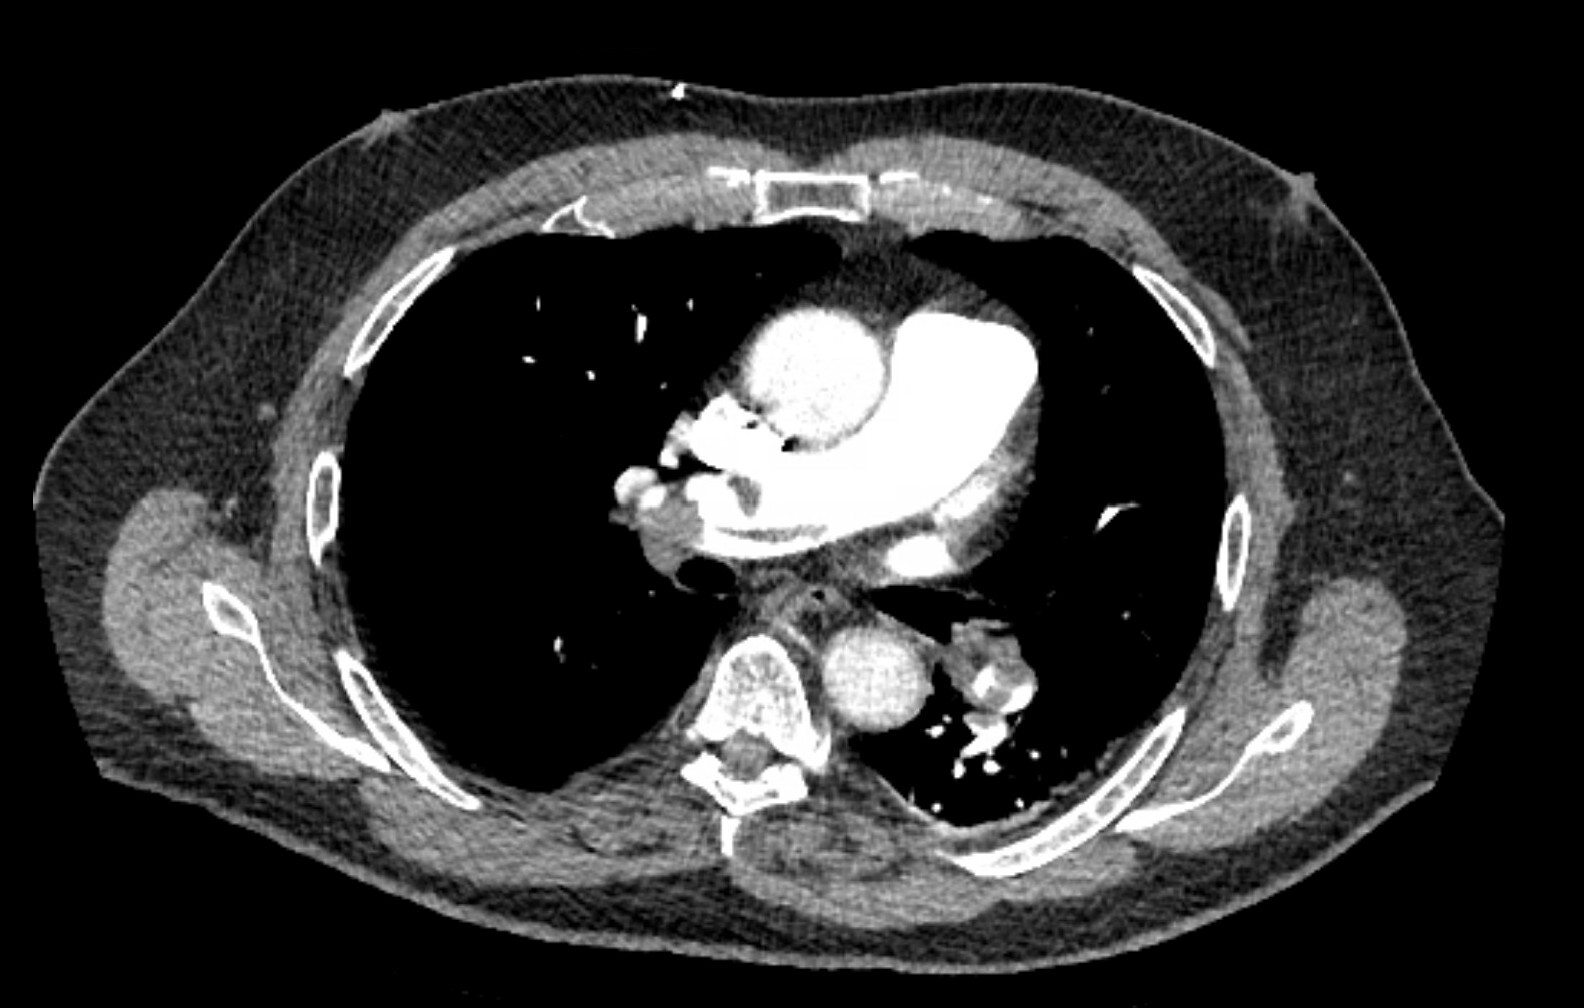

A 61-year-old woman with a history of hyperlipidemia, hypertension, stage 1 chronic kidney disease, and a baseline creatinine level of 1.5 mg/dL (132.6 μmol/L) presented yesterday with acute hypoxic respiratory failure from multilobar pneumonia. She underwent intubation last night, after which she developed mild shock, and she currently is receiving a 0.15 μg/kg/minute norepinephrine infusion. This morning, her ventilator settings have stabilized with assist control volume control with tidal volume of 350 mL, PEEP of 10 cm H₂Ο, and FiΟ₂ of 0.6. Her urine output has decreased, and she has been making only 5 to 10 mL of urine an hour for the last 12 hours. Her laboratory tests are notable for the results shown in Figure 1. Enteral feeding was started this morning at a trophic rate of 10 mL/hour.